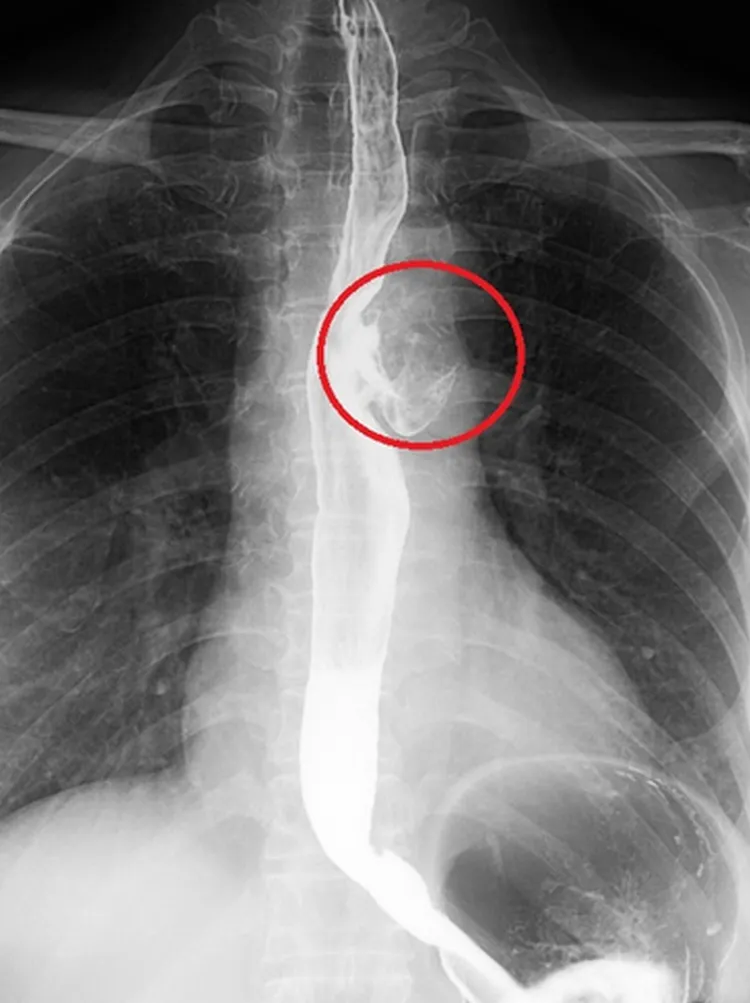

61歲婦人食道長「憩室」。台北慈濟醫院提供